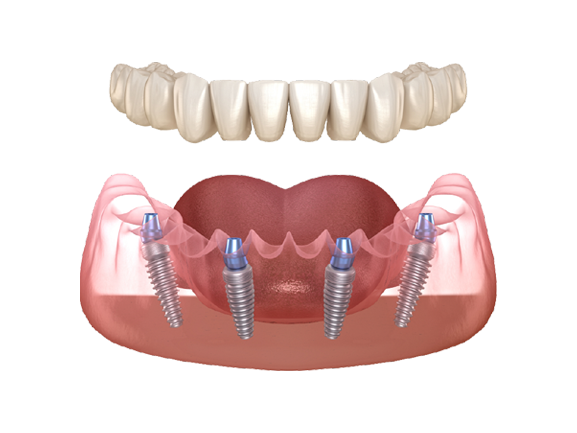

FULL MOUTH IMPLANTS

Patients who need to replace a full upper and/or lower set of teeth can now receive full mouth implants.

One of our Doctors will place 4 implants and then attach a full set of teeth on top. This procedure is commonly referred to as All-On-4.